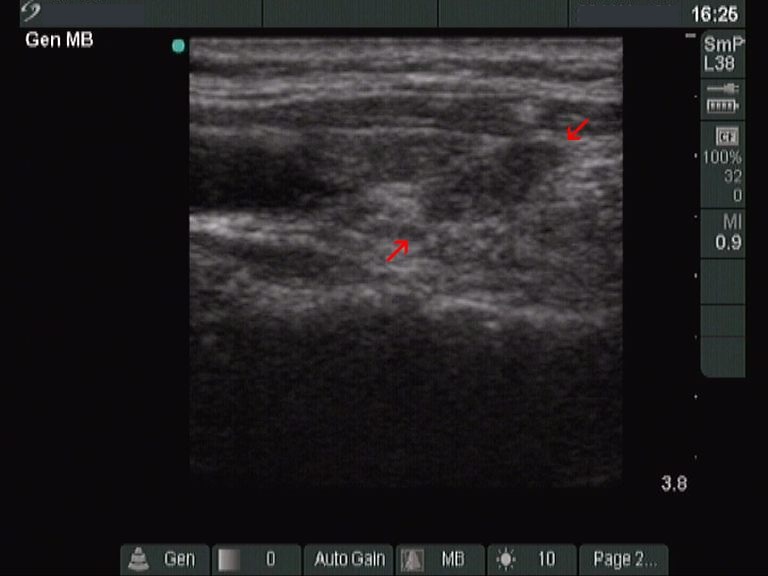

Third row: ultrasonographic pictures 1 year later. The size of the lesion became 6x6x12 mm (width x depth x length).